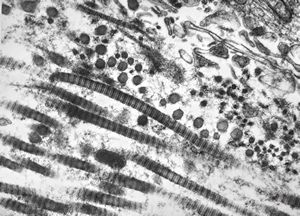

M, 43y. | myeloid leukemia … Auer bodies

M, 43y. | myeloid leukemia … Auer bodies

M, 43y. | myeloid leukemia … Auer bodies